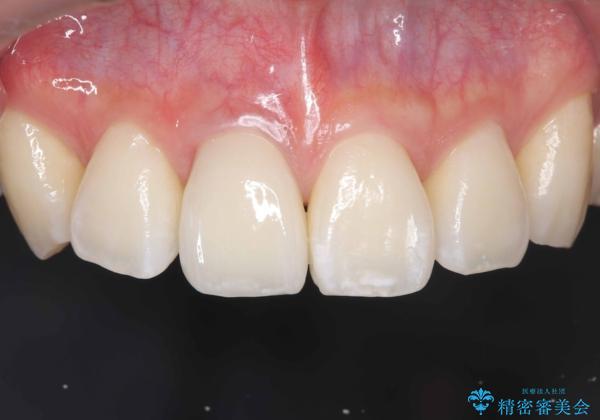

【オールセラミッククラウン】前歯の見た目が気になる!

- 前歯の見た目が気になるを主訴に来院された患者様です。

根管の充填物も不十分だったため根管治療からやり直しオールセラミッククラウンで治療を行いました。

根管の中が空洞のままで被せ物と歯のきわも合っておらず適合が悪い状態でした。根尖部付近にはパーフォレーションリペア修復の痕がありました。バイオシーシーラーを使用しシングルポイント法で充填しました。空洞があると細菌が増える環境になってしまうので、根管治療からやり直し、緊密に充填しました。被せ物の見た目も大変満足していただけました。